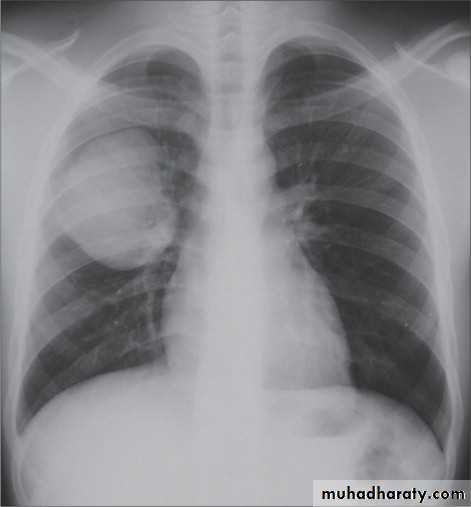

Pericardial effusion Globe shape

17. Globe shape heart (pericardial effusion )